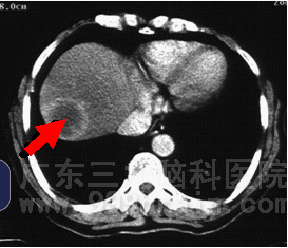

来自江西的殷某,3月前发现腹部包块,质地硬,无压痛,进食后有稍许腹胀感,未出现厌食油腻及全身乏力等不适,至当地医院检查诊断为肝癌,行介入治疗。治疗后一月复查示肿瘤较前增大。患者经多方了解后转至广东三九脑科医院求治,肿瘤综合治疗中心李明众教授予病人查体时发现患者肝右叶包块,巩膜轻度黄染,查肿瘤标志物甲胎蛋白值远远高于正常,患者除有进食后腹胀感外,其他一般情况良好。肿瘤综合治疗中心专家组审慎讨论了病例,经研究讨论决定给患者行适形放疗,放疗期间同步予化疗。放疗完成55Gy后复查CT片示巨块型肿瘤已消失,肿瘤标志物甲胎蛋白值恢复正常,患者自诉上腹饱胀感明显好转。

▲治疗前